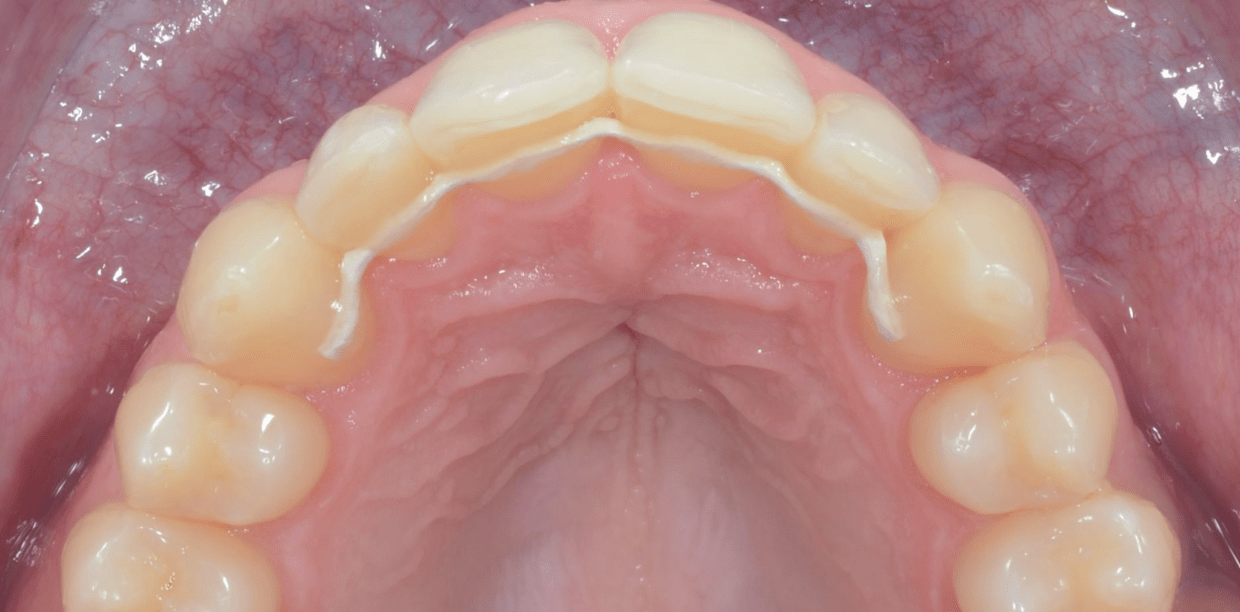

Simple - White

Simple - White

Simple - White

Simple - White

Simple - White

Simple - White

Simple - White

Simple - White

Simple - White

Simple - White

Simple - White

Simple - White

Simple - White

Simple - White

Simple - White

Simple - White